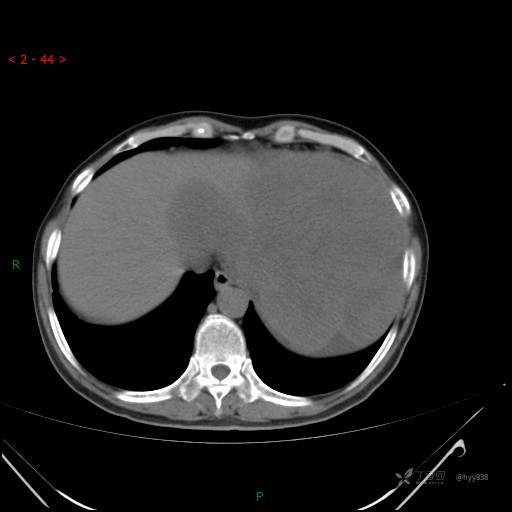

腹部CT平扫